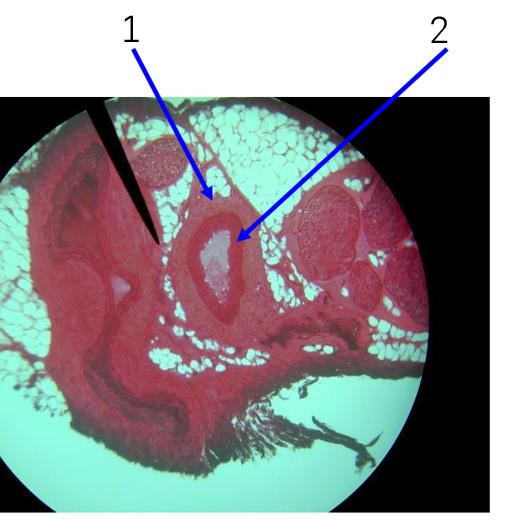

Name number 1

Tunica externa

Name number 2

Tunica media